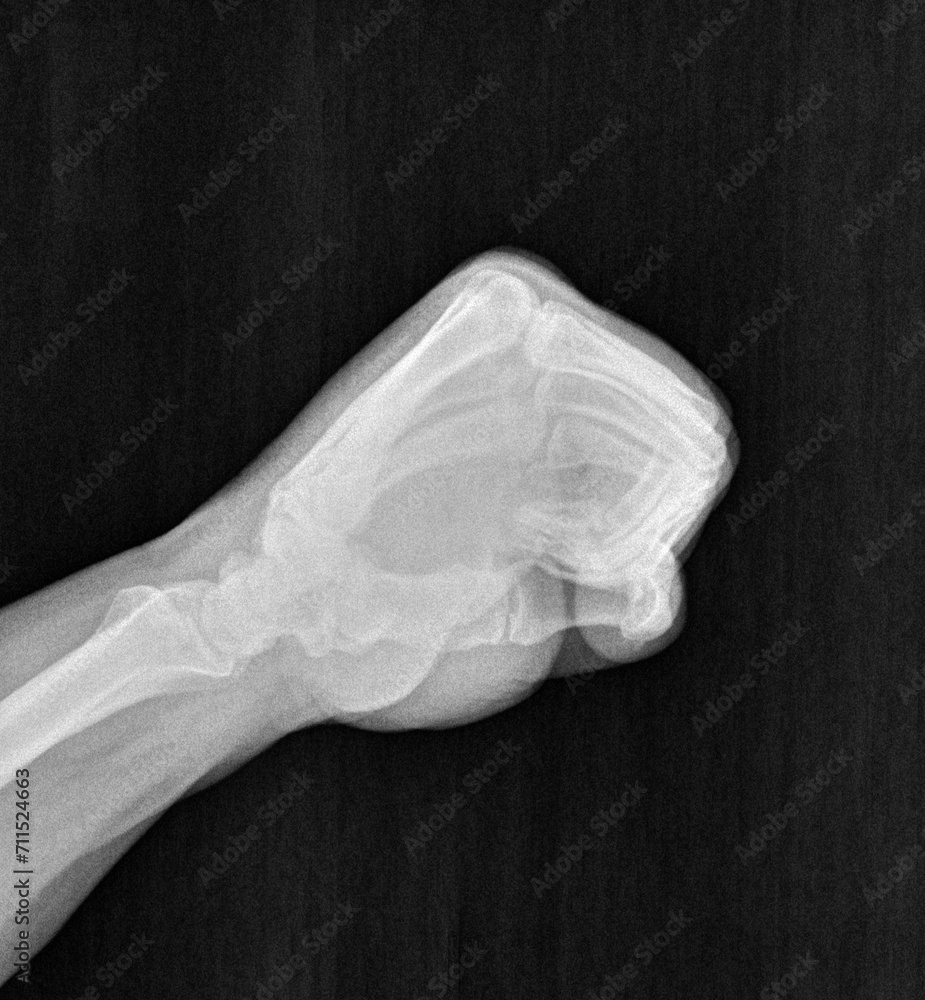

Clenched Fist Radiograph . If widening is present, think scapholunate dissociation and consider obtaining a “clenched fist” view. look specifically at scaphoid and lunate for widening. Mid and proximal metacarpals, carpals, distal radius and ulna, and associated joints;. Pa views with wrist in ulnar deviation (causes intercalated segment extension) scaphoid. — clenched fist views. dynamic ap view (clenched fist view) the ap view can be used dynamically [figure 15] by asking the patient to clench his fist.

Mid and proximal metacarpals, carpals, distal radius and ulna, and associated joints;. Pa views with wrist in ulnar deviation (causes intercalated segment extension) scaphoid. dynamic ap view (clenched fist view) the ap view can be used dynamically [figure 15] by asking the patient to clench his fist. If widening is present, think scapholunate dissociation and consider obtaining a “clenched fist” view. look specifically at scaphoid and lunate for widening. — clenched fist views.